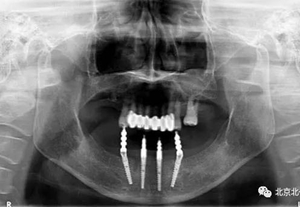

圖十五:術(shù)后即刻拍X片

圖二十一:半年后復(fù)查X片

圖二十二:2015年到2016年復(fù)查時(shí)X片 ,有圖有真相

沒有假貨,貨真價(jià)實(shí),完成三年復(fù)查。

圖二十三:有圖有真相。

圖二十四:2017年11月復(fù)查時(shí)照片,植體很穩(wěn)定, 無骨吸收。